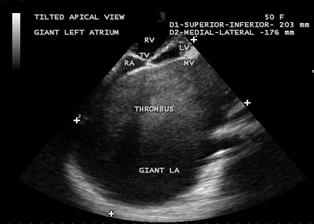

Figure 22. Tilted apical view showing the thrombus occupying the entire Left atrium in a 50-year old female.

Figure 23. Tilted apical view showing the giant thrombosed left atrium in a 50-year-old female measuring as 203 x 176 mm.